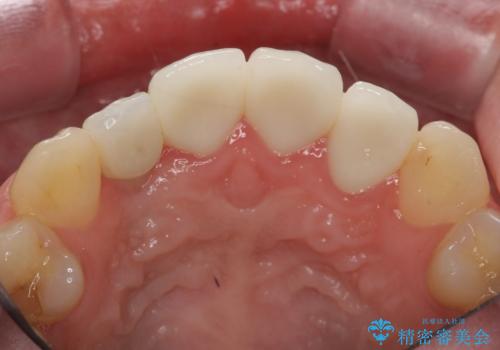

充填されたコンポジットレジン・再発した虫歯を神経に影響が出ないよう丁寧に除去し再充填をしたのちオールセラミッククラウンで前歯の審美性を回復します。

- 33万円(仮歯・ジルコニアクラウン×3)費用は治療当時の料金となります

前歯のコンポジットレジン修復は、経年劣化し虫歯の再発しやすい素材なので定期的なX線検査が推奨されます。